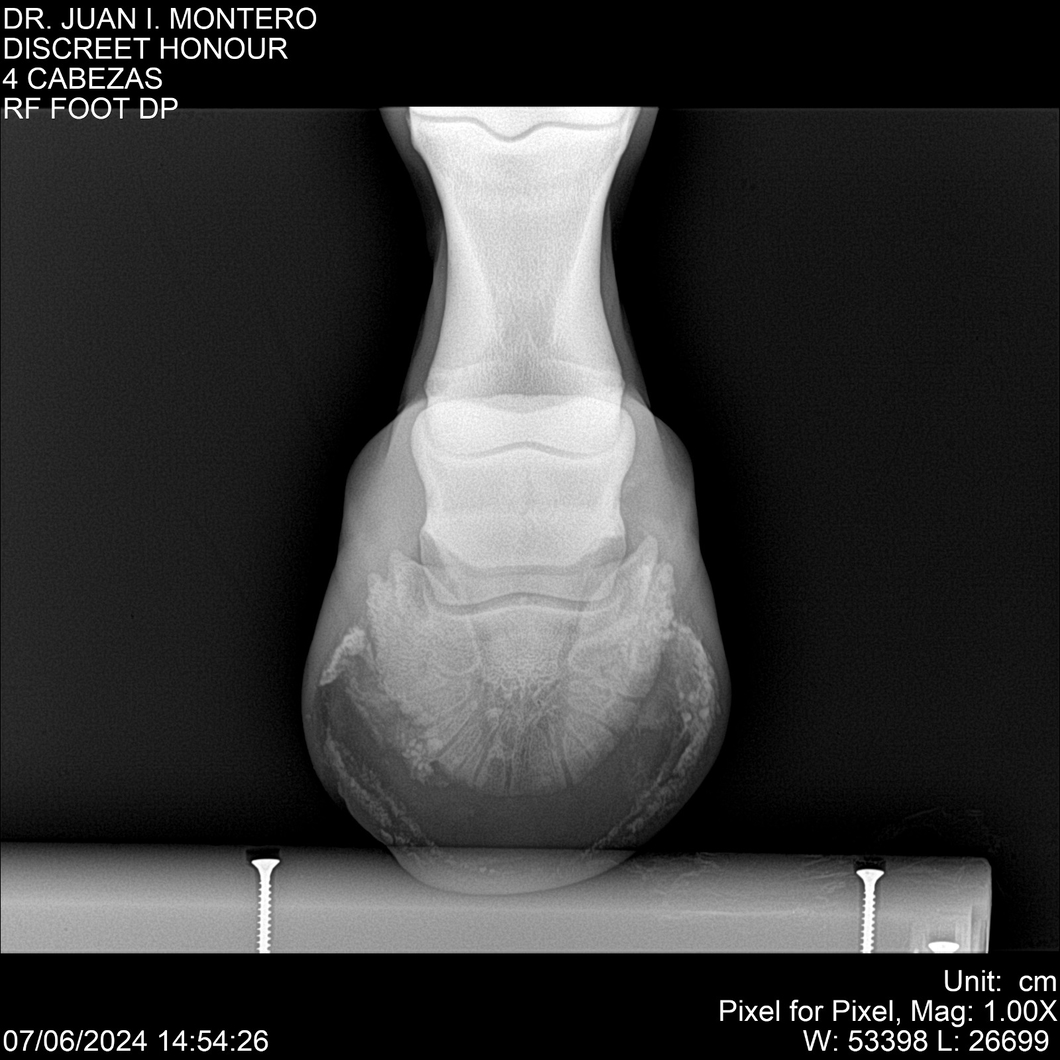

LOTE 6, DISCREET HONOUR 🔥 🔥 🔥 Lote Anterior Volver al remate Lote Siguiente Ficha Contacto Montevideo - Ficha del Lote Identificador: #281093 Categoría: Yeguarizos Montevideo - 82 Visualizaciones ClicData Contacto Empresa: Abelenda N. R., Walter Hugo Nombre*: Teléfono* : E-mail* : Mensaje Enviar Registrese gratis Este contenido Exclusivo está disponible sólo para usuarios registrados Ingresar